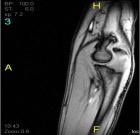

20 year old female who two months prior sustained a fall on to her right outstretched upper extremity and sustained an olecranon fracture for which she has undergone nonoperative management. She recalls that she had been experiencing discomfort in the right elbow prior to sustaining her injury.